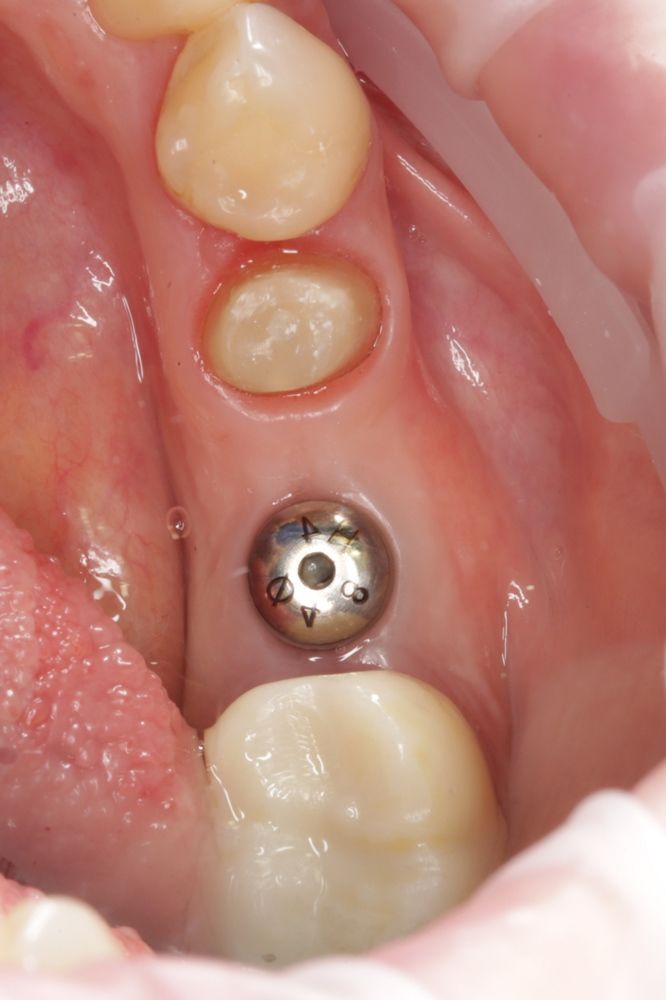

Имплантация жевательных зубов,

это самая востребованная операция.

Анна Анатольевна Кушнарева

хирург - имплантолог

рентген имплантатоы

фото коронок